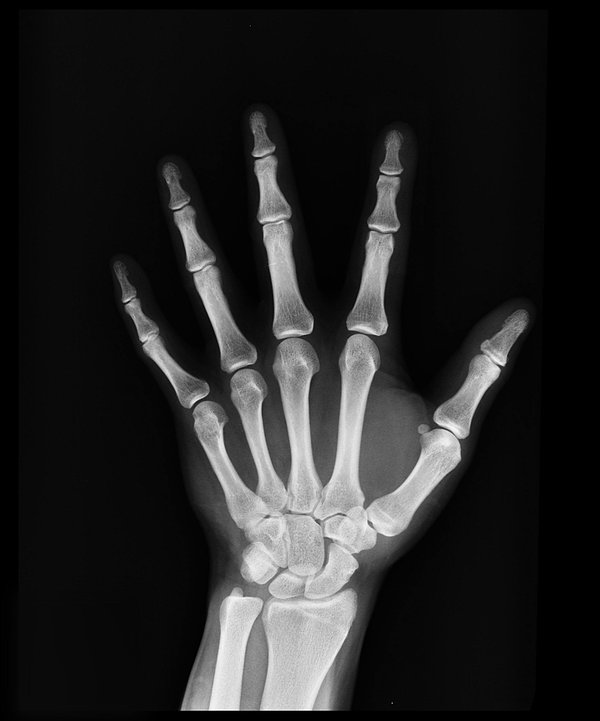

L’ostéoporose se caractérise par une fragilité osseuse excessive, qui augmente le risque de fracture. Heureusement, des gestes simples au quotidien peuvent vous aider à la prévenir. L’alimentation joue un rôle central dans cette prévention. Une consommation adéquate en calcium et vitamine D, une sélection judicieuse de produits laitiers et d’aliments riches en protéines sont autant de leviers à actionner. Alors, que mettre dans votre assiette pour renforcer vos os ?